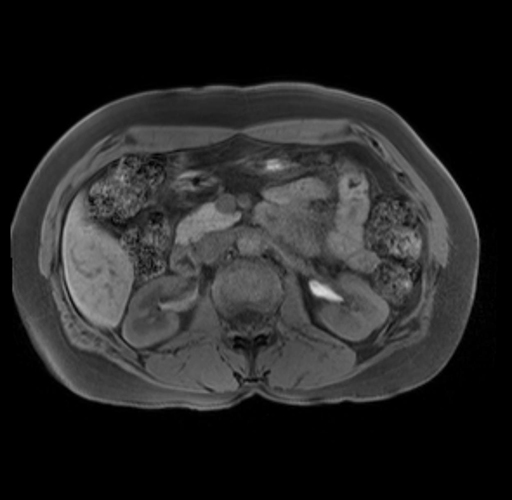

Imaging Analysis

Look through the patient's CT scan to identify any areas of concern for the necessary procedure.

Based on your CT findings, which issue(s) are present and would give reason for "planned slowing down moment(s)" in this case?